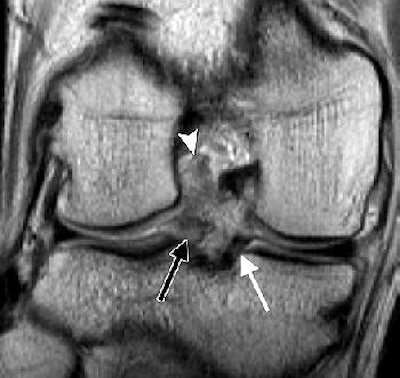

![]() |

| LMRT and meniscus extrusion in a 20-year-old man with ACL tear. Above, coronal posterior and midknee (below) intermediate-weighted (4083/17) fast SE MR images of the right knee show ACL tear (arrowhead), LMRT (black arrow), and normal medial meniscus root (thin white arrow). The distance between the two vertical lines in image below indicates meniscus extrusion of 3.7 mm (thick white arrow). |